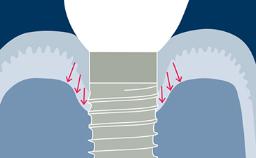

Todos os profissionais de saúde que fazem cirurgia de implante encontrarão complicações durante toda a vida profissional. Tais complicações podem ocorrer por várias razões diferentes, mas a maioria pode ser explicada como percalços ou erros cirúrgicos e/ou protéticos. Este módulo de aprendizado fornecerá uma visão geral das complicações cirúrgicas mais frequentes associadas à instalação do implante e discutirá o manejo em termos de medidas preventivas e estratégias de tratamento.

- descrever as complicações cirúrgicas mais frequentes relacionadas à instalação do implante